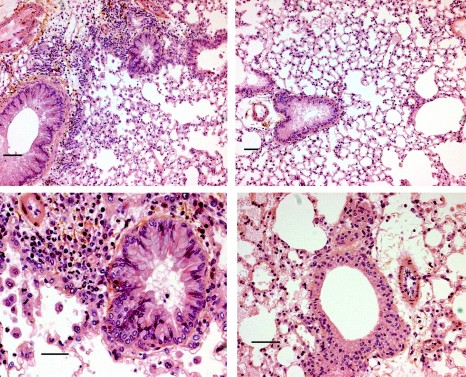

Entre 1% et 3% de la population mondiale souffre d’asthme sévère. « Il est caractérisé par une gêne respiratoire permanente, une activité physique limitée, des crises nocturnes fréquentes, et des crises d’asthmes prolongées », explique les chercheurs de l’INSERM (Centre de Recherche Cardio-thoracique de Bordeaux). « L’obstruction des bronches est alors à l’origine de la diminution importante de la capacité respiratoire. Cette obstruction est due à un remodelage des voies aériennes et notamment à l’augmentation de l’épaisseur du muscle lisse bronchique (MLB) qui les tapisse. »

Les chercheurs – qui avaient déjà montré son efficacité in vitro – ont mesuré in vivo l’effet anti-prolifératif du gallopamil sur 31 patients souffrant d’asthme sévère. Ainsi, les données montrent une réduction significative du MLB chez les asthmatiques traités par rapport au groupe placebo. En conséquence, il a permis une diminution significative de l’épaisseur de la paroi bronchique.